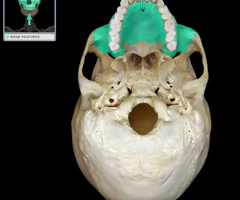

Palatine process of maxilla (helps form hard palate with palatine bones)

Palatine bones

Vomer

Vomer

Occipital condyles (articulates with superior articular surfaces of atlas)

Foramen magnum (“big hole” for the spinal cord)

Optic canals (optic nerve)

Optic canals (optic nerve)

Maxilla bone